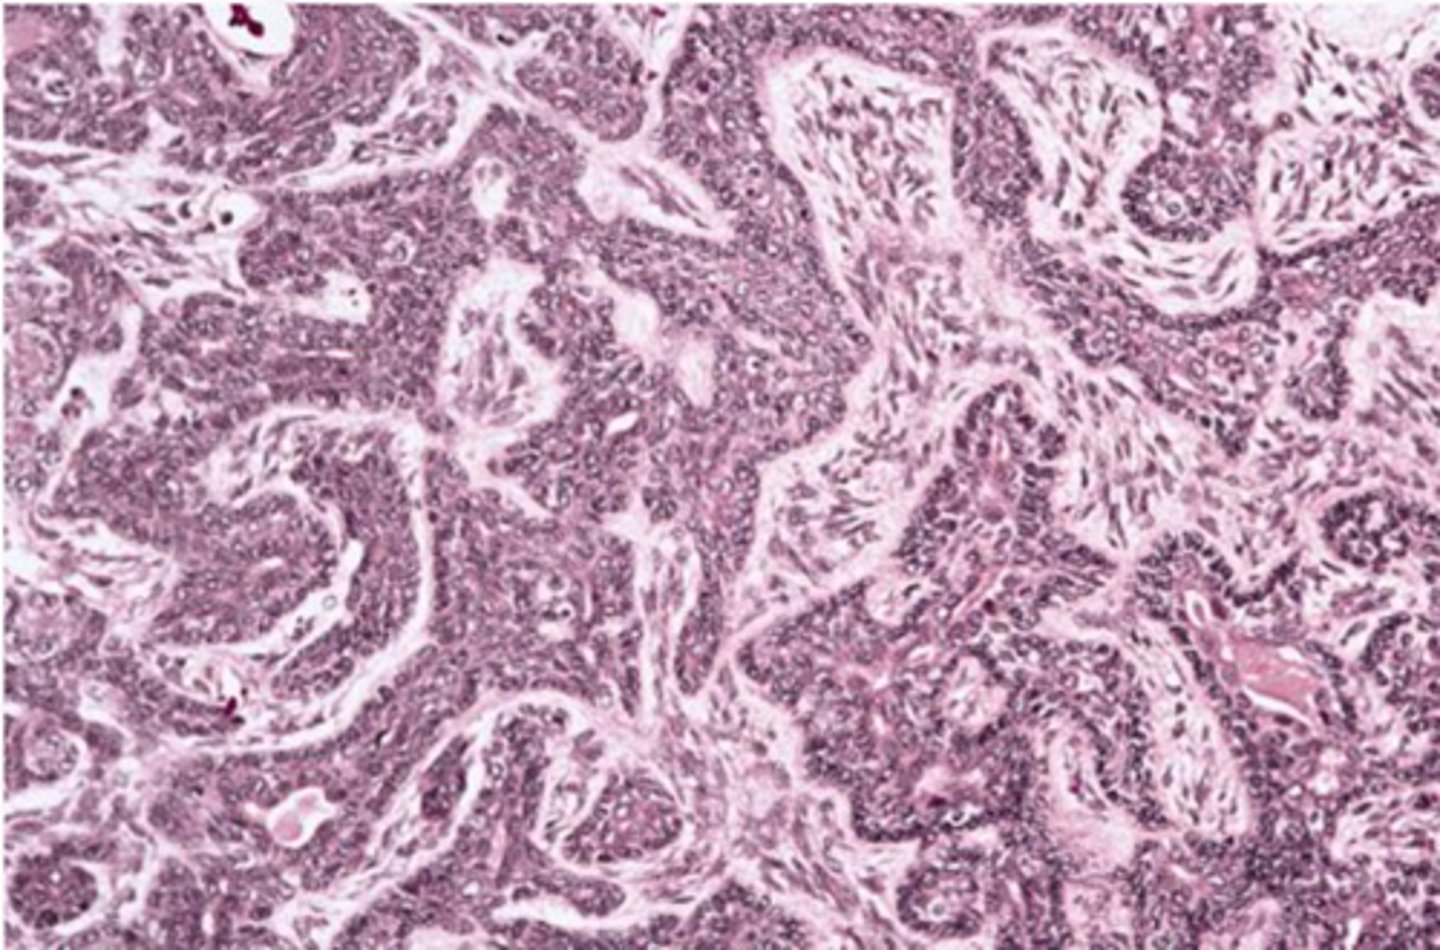

Polymorphous Adenocarcinoma

-Various histologic patterns

-Cells line up in single file line "Kindergarten filing"

-Perineural and Perivascular invasion